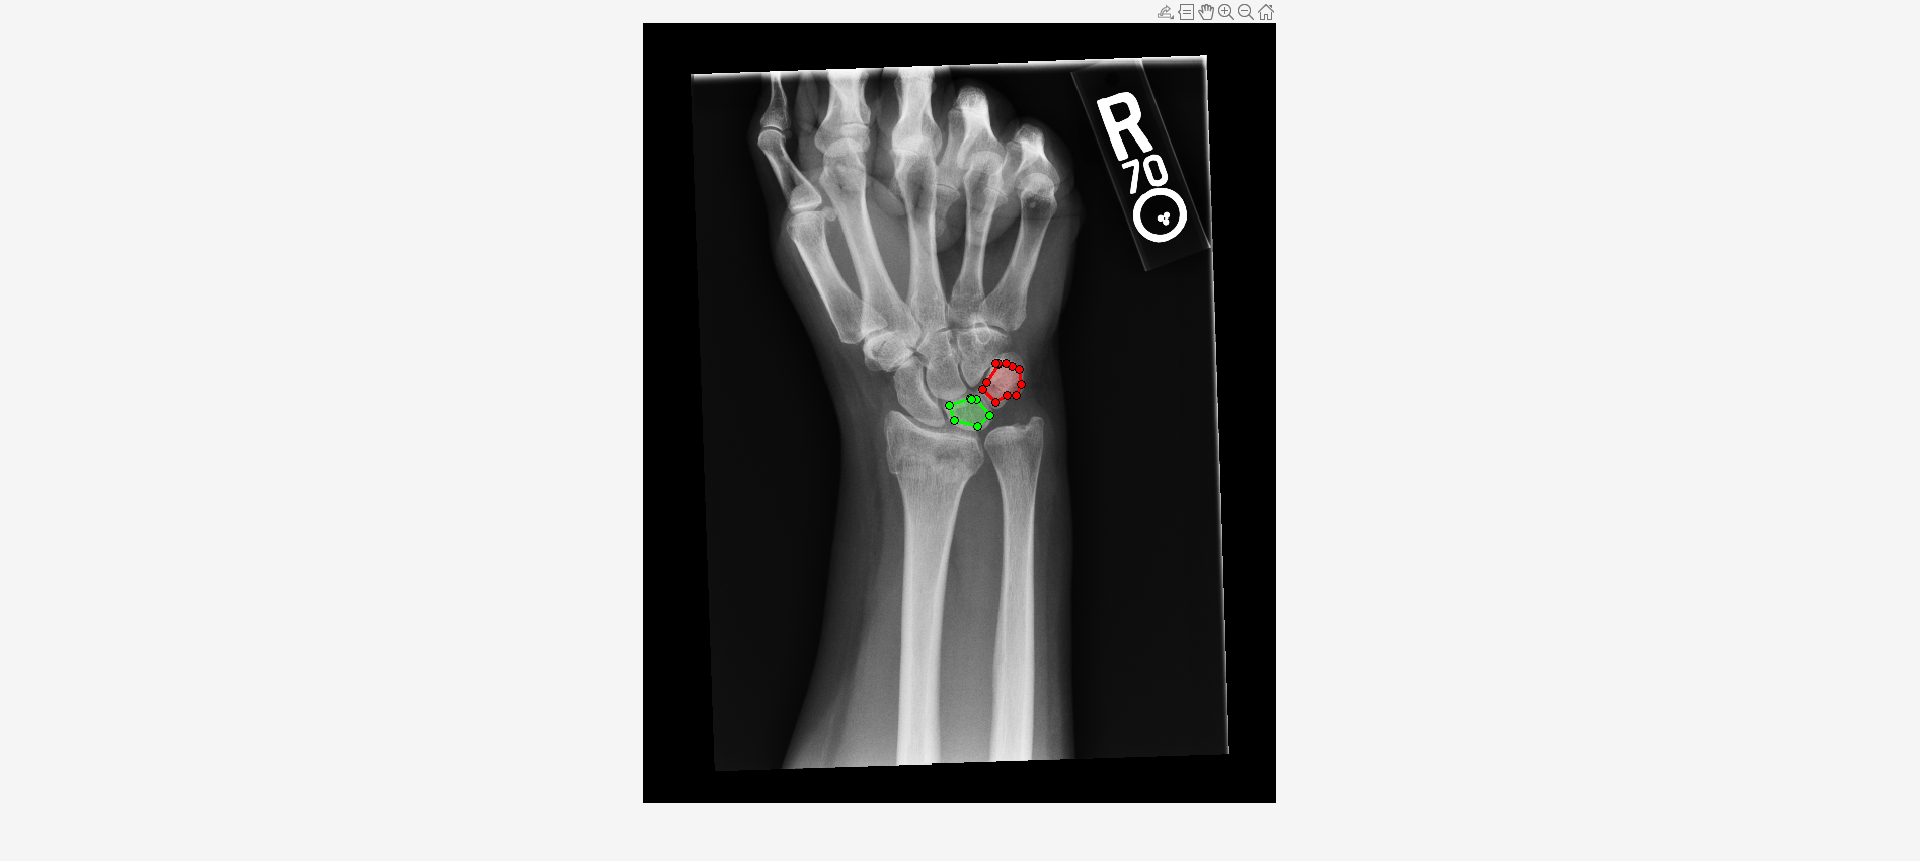

Load an X-ray image into the workspace as a medicalImage object. Visualize the image.

data = medicalImage("forearmXrayImage1.dcm");

I = data.Pixels;

figure

imshow(I,[])Draw two regions of interest (ROI) in the X-ray image. Create masks from the ROIs.

roi1 = drawassisted(Color="g"); roi2 = drawassisted(Color="r");

mask1 = createMask(roi1,I); mask2 = createMask(roi2,I);

Create an ROI label matrix, using different labels for the two ROIs. Create a medicalImage object of the ROI label data.

mask = zeros(size(I));

mask(mask1) = 1;

mask(mask2) = 2;

info = dicominfo("forearmXrayImage1.dcm");

roi = medicalImage(mask,info);Create a radiomics object from the X-ray image data and ROI label data.

Compute selected features for both ROIs.

F = selectFeatures(R,["MeanIntensity2D","ContrastAveraged2D"])

F=2×3 table

LabelID MeanIntensity2D ContrastAveraged2D

_______ _______________ __________________

"1" 2314.4 122.85

"2" 2438.5 104.57